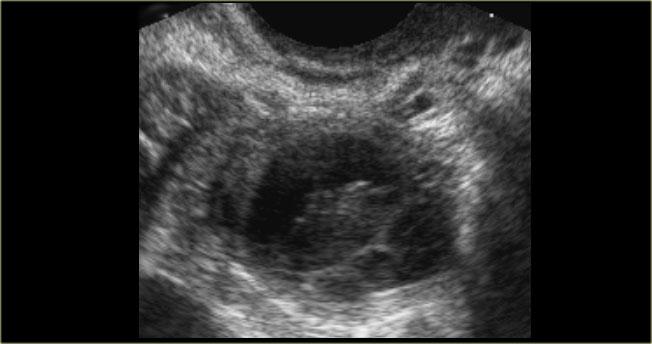

Hình ảnh siêu âm cho thấy hai nang đơn giản ở buồng trứng phải với mô đệm buồng trứng ở giữa.

Các mạch máu xung quanh bình thường và không có vách ngăn có mạch máu.

Đây là các nang nang trứng đơn giản ở phụ nữ tiền mãn kinh.